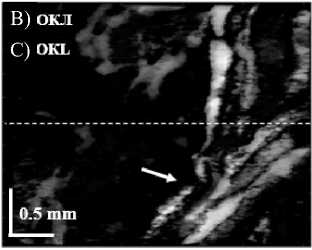

получаемых в течение 26 с объемных изображений – 2,4×2,4×1,8 мм. Кросс-поляризационная ОКТ-модальность позволяет строить 2 вида изображений: на одних отображается общая структура ткани (как в поперечном сечении, так и при виде сверху), на других сигнал появляется только от компонентов, изменивших поляризацию зондирующего излучения на ортогональную. Режим ОКЛ основан на анализе вариации спекловой картины ОКТ-сигнала и позволяет визуализировать лимфатические сосуды с функционирующим током лимфы [8, 13] (рис. 2).

Рис. 2. ОКТ-скан стенки тонкой кишки (стрелкой указаны интрамуральные лимфатические сосуды) (А), программная обработка рисунка (Б); ОКТ в режиме лимфографии (стрелкой указаны функционирующие лимфатические сосуды) (В)

Fig. 2. OCT scan of the small intestinal wall (the arrow indicates intramural lymphatic vessels) (A), digital image processing (B); OCT lymphography mode (the arrow indicates functioning lymphatic vessels) (C)

ниям (рис. 3). В то же время лимфатическая система интактной кишечной стенки представляет собой развитую сеть сосудов разного диаметра, сопровождающих артерии и вены.

Показатель средней плотности лимфатической сети сосудов в интактной кишке составил 2,29 % [2,04; 2,73]. Надо отметить, что максимум данного показателя достиг 10 %. Подобное аномально высокое значение, вероятнее всего, связано с возникновением отека кишечной стенки в ответ на агрессию. Спустя 3 ч после резекции симпатических ганглиев зафиксировано статистически незначимое уменьшение числа и толщины, визуализируемых на ОКТ-изображениях лимфатических

сосудов, при этом плотность последних снизилась до 1,8 % [1,12; 1,94] (p=0,052) (рис. 4).

Рис. 4. ОКТ-скан стенки тонкой кишки с функционирующими в ней лимфатическими сосудами (показаны стрелкой) (А1); ОКТ в режиме лимфографии (стрелкой указаны функционирующие лимфатические сосуды) (А2); ОКТ-скан стенки тонкой кишки после травмы со спавшимися лимфатическими сосудами (показаны стрелкой) (Б1); ОКТ в режиме лимфографии (стрелкой указано нарушение тока лимфы) (Б2)

Fig. 4. OCT scan of the small intestinal wall with functioning lymphatic vessels (indicated by the arrow) (A1); OCT lymphography mode (the arrow indicates the functioning lymphatic vessels) (A2); OCT scan of the small intestinal wall after injury with collapsed lymphatic vessels (indicated by the arrow) (В1); OCT lymphography mode (the arrow indicates impaired lymph flow) (В2)